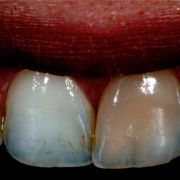

After bleaching, composite is layered (arrow) from inside labially to restore the lost tooth structure from the previous access and to modify the light reflection within the tooth.

The large access cavity decreased in diameter after the inside composite layering at the labial surface.

To avoid improper composite curing due to deep access cavity, fiber post is placed instead to fill in the access. The post is now snuggly fitted.